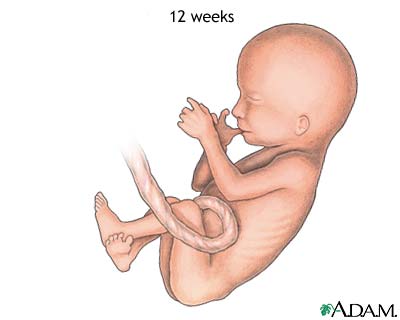

Weeks 11 to 14

- Your baby's eyelids close and will not reopen until about the 28th week.

- Your baby's face is well-formed.

- Limbs are long and thin.

- Nails appear on the fingers and toes.

- Genitals appear.

- Your baby's liver is making red blood cells.

- The head is very large -- about half of your baby's size.

- Your little one can now make a fist.

- Tooth buds appear for the baby teeth.